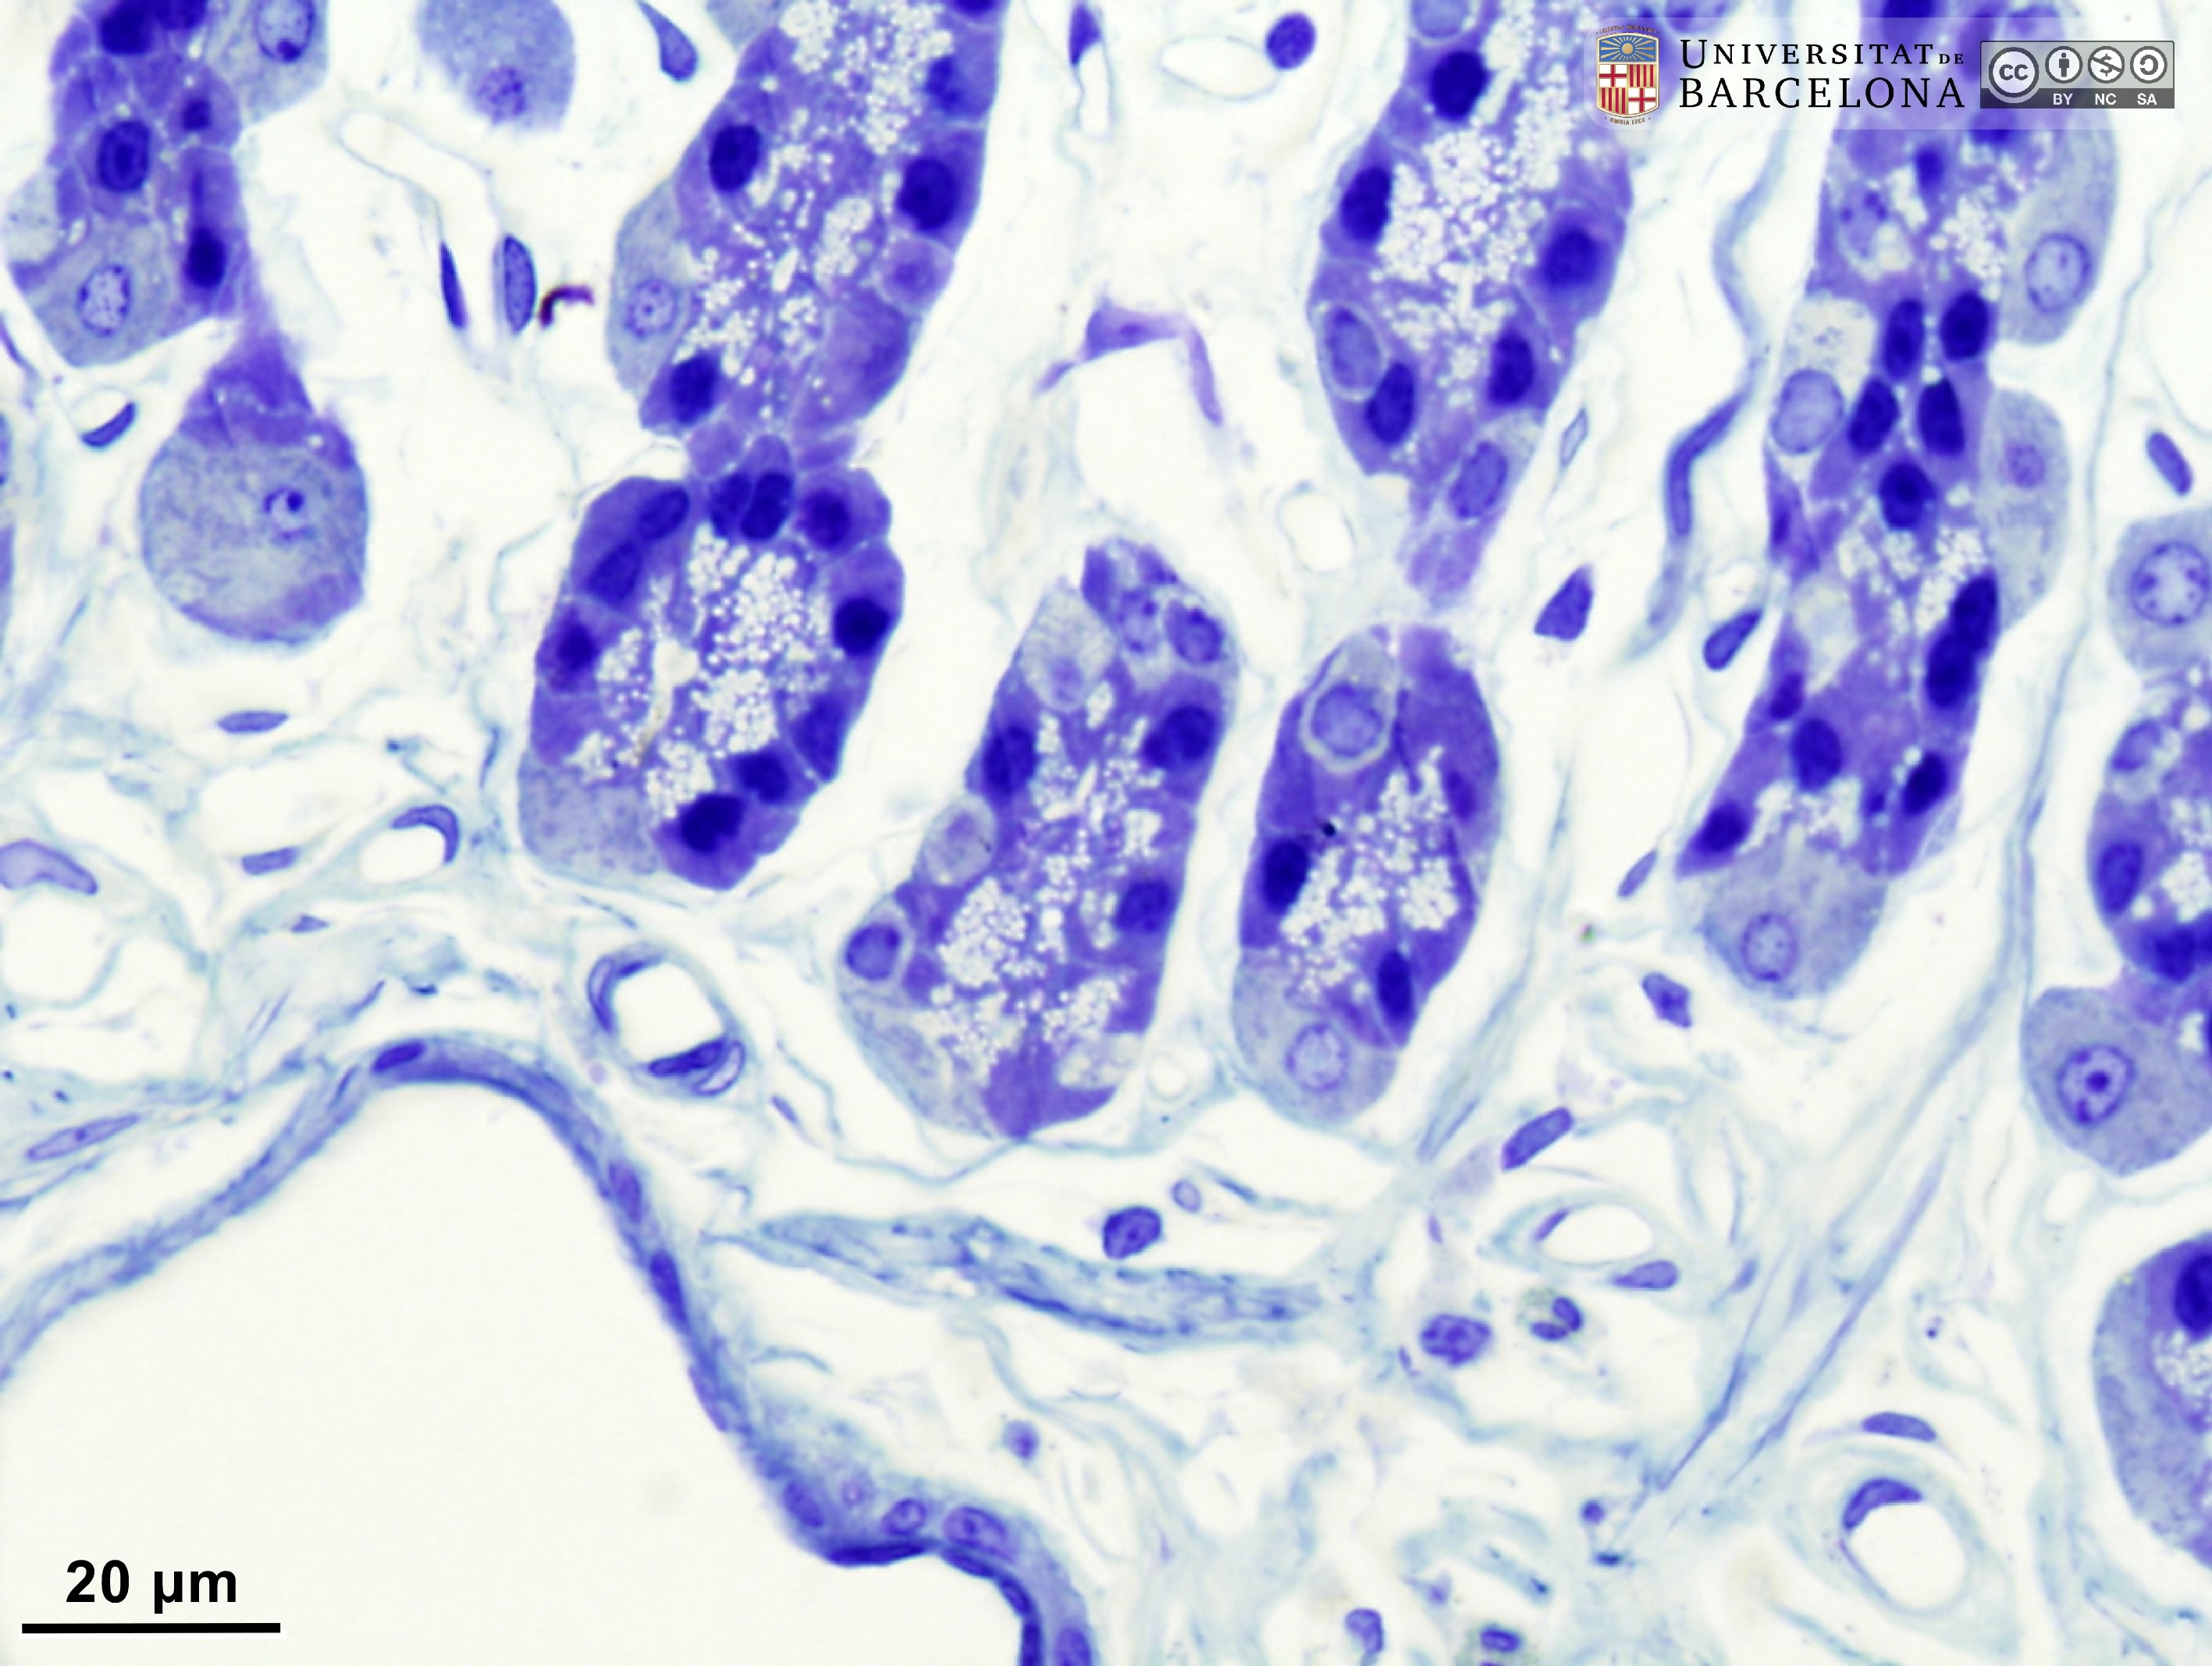

Stomach: histological organisation of the gastric wall

[ENG] A collection of micrographs illustrating the organisation of the stomach in rats. The layers of the gastric wall and their components –such as blood vessels, fibres and cell types– are shown in paraffin sections stained with hæmatoxylin-eosin stain or van Gieson trichrome. Semithin sections 2 µm thick were stained with toluidine blue. This collection complements the micrographs published by Dr Elena Sagristà i Mateo https://hdl.handle.net/2445/60213 — See also: https://diposit.ub.edu/dspace/browse?type=author&value=Sagrist%C3%A0+i+Mateo%2C+Elena

Cite as: Pérez-Clausell J (2025). Stomach: histological organisation of the gastric wall. Universitat de Barcelona. Departament de Biologia Cel·lular, Fisiologia i Immunologia. Dipòsit digital UB [consulted on 7/23/2025] https://hdl.handle.net/2445/222504